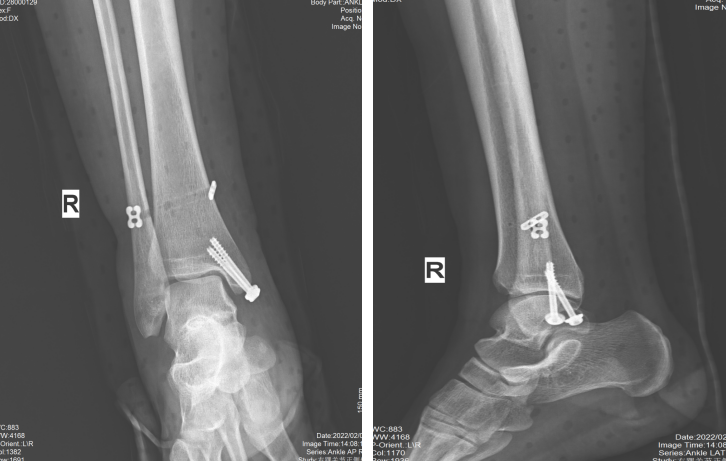

上图为患者术后X线片检查图像,外踝骨折行钢板螺钉固定,下胫腓联合损伤行带袢钢板固定。图A为正位片;图B为侧位片;图C为踝穴位片。(来自参考文献5)

上图为踝关节骨折伴下胫腓联合损伤患者,图1、图2为下胫腓螺钉固定;图3、图4为下胫腓带袢钢板固定。(来自临床病例)